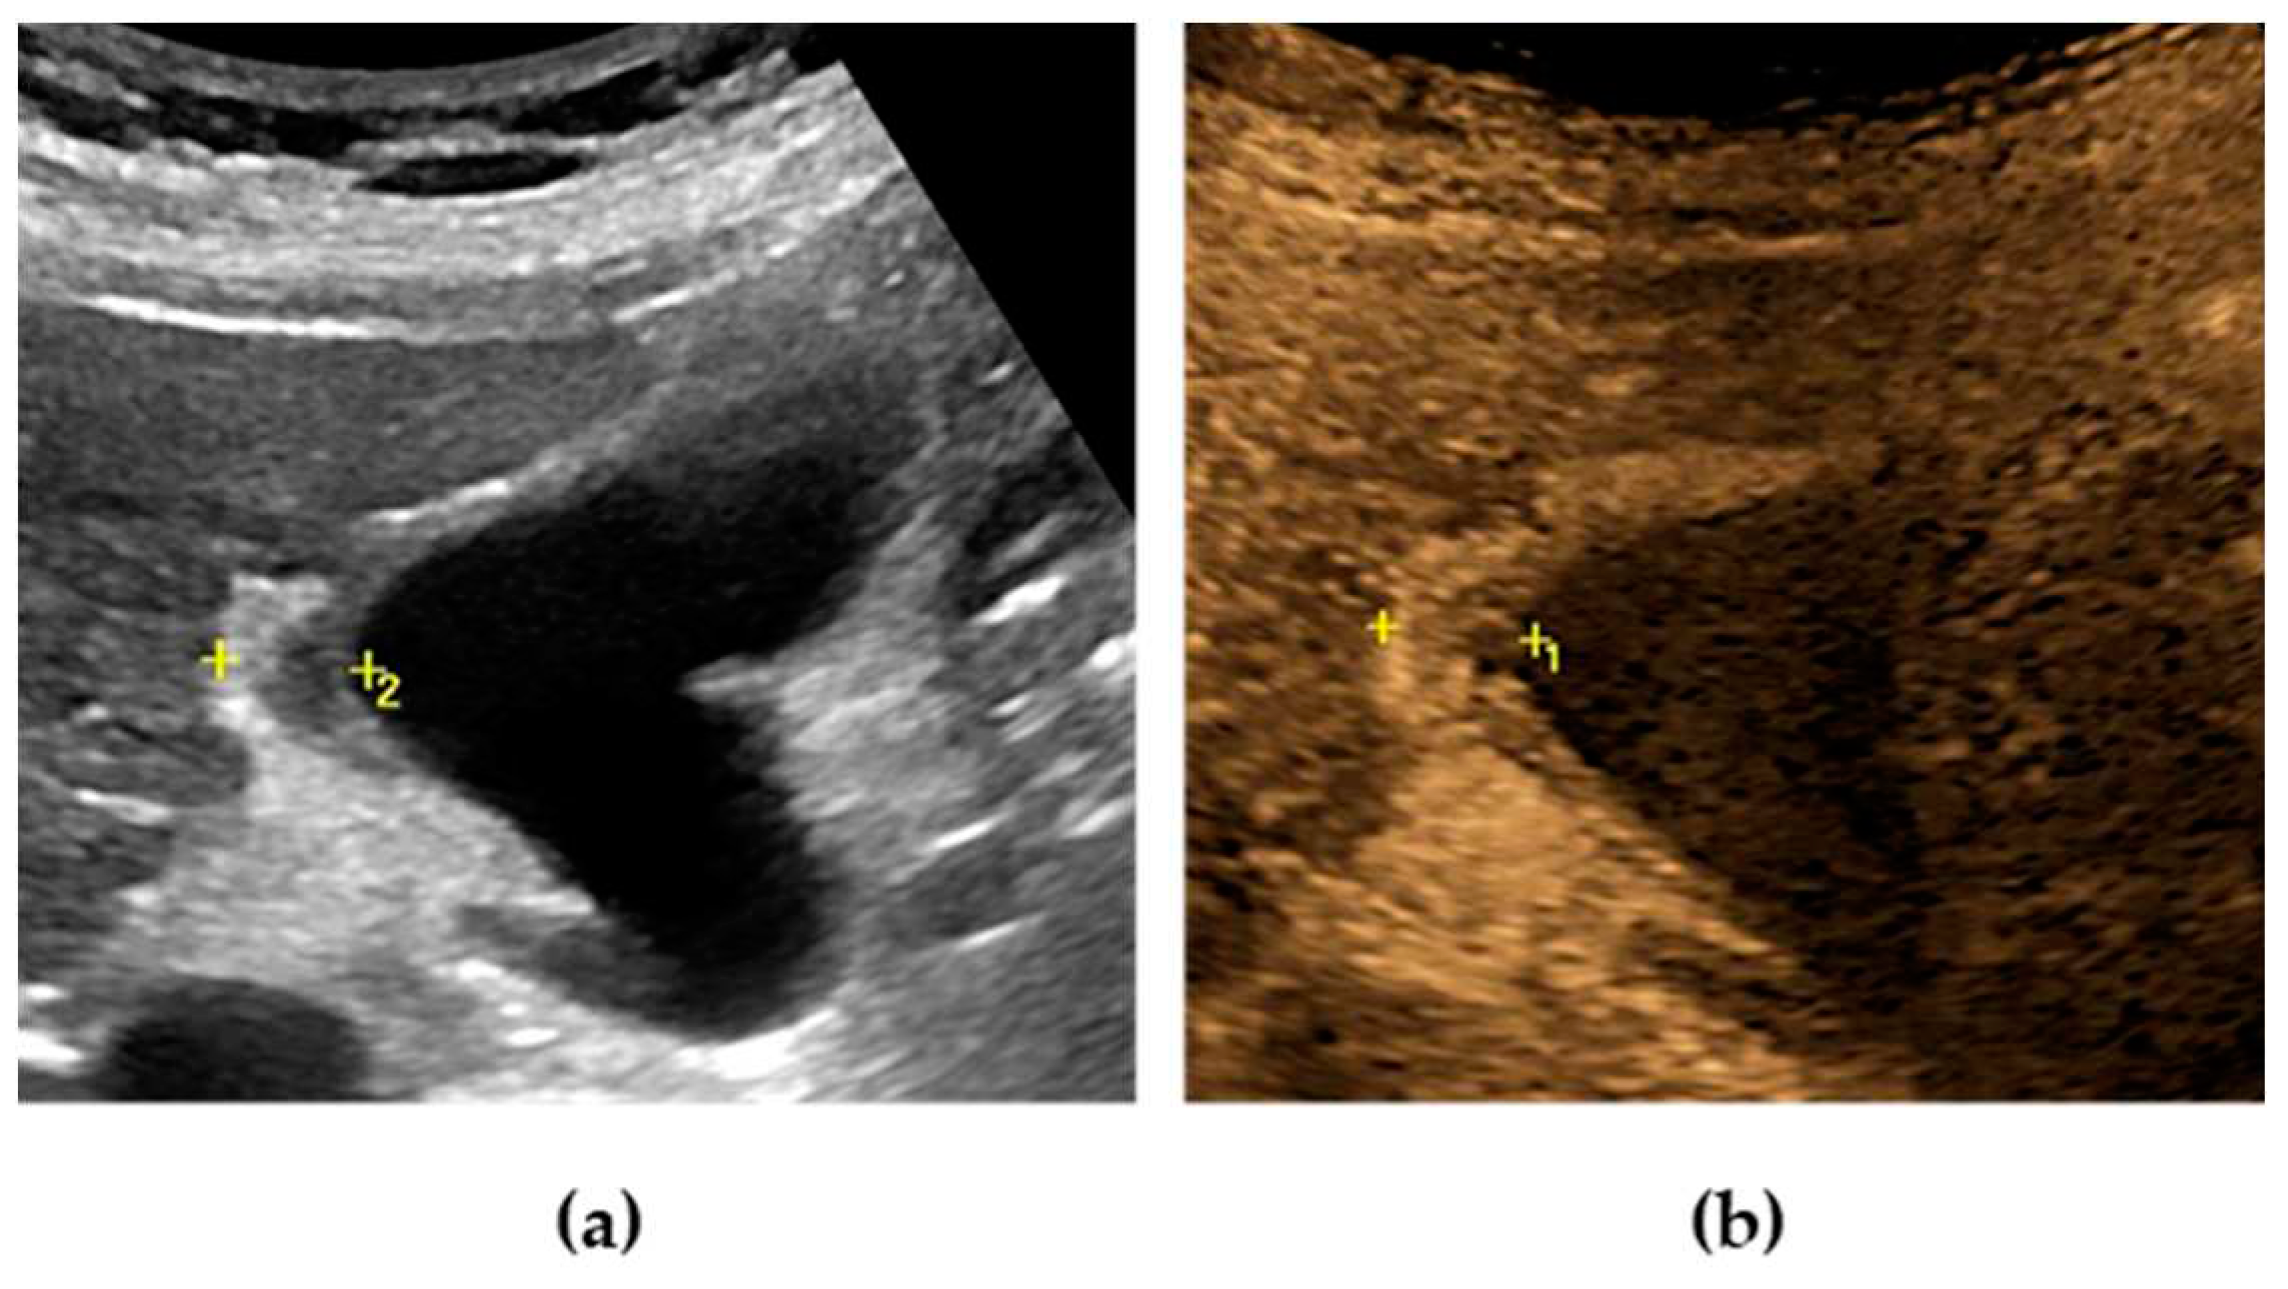

The US typical appearance of gallstones is an echogenic focus in the gallbladder lumen that casts a posterior acoustic shadow and changes position according to the variation of patient decubitus (Figure 1).[3] Stones smaller than 2 or 3 mm may be difficult to visualize, especially if isolated. Gallstones typically produce complete shadowing without reverberation because most of the ultrasound is absorbed by the stone. Rarely, reverberation artifacts may be seen posterior to calcified stones if they contain gas within fissures. [1]

Typically, biliary sludge is a slight sonographic finding,[1] which appears as non-shadowing echoes with an indefinite shape that tend to layer in the most declivous portion of the gallbladder. Biliary sludge forms a horizontal level that moves slowly, according to changes in patient’s decubitus (Figure 1). [1,2]

On CD, the highly reflective surface of the stones, particularly in case of cholesterol stones, can produce the typical “twinkling artifact”, characterized by a mosaic of colored pixels posterior to the stone. [7,8]